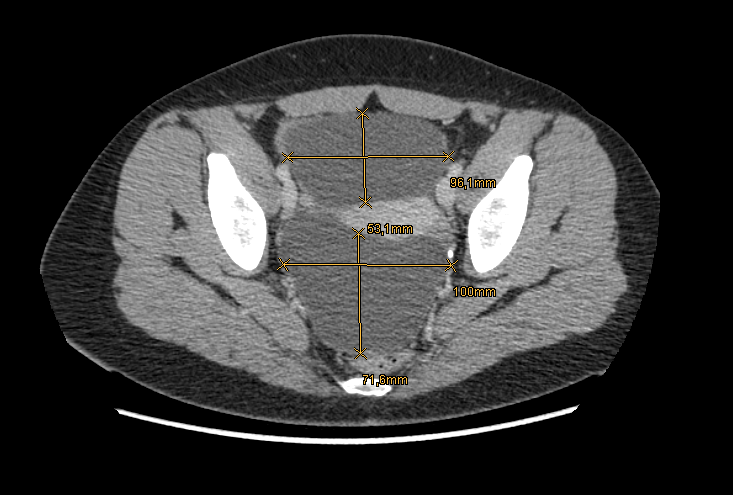

La efectuarea investigatiilor imagistice s-a evidentiat prezenta a doua formatiuni chistice ovariene de 11 cm si respectiv 14 cm. Se ia in considerare diagnosticul de chist ovarian atunci cand dimensiunea formatiunii este mai mare de 2 cm.

Chist ovarian CT masurat longitudinal:

Chist ovarian CT masura transversal: